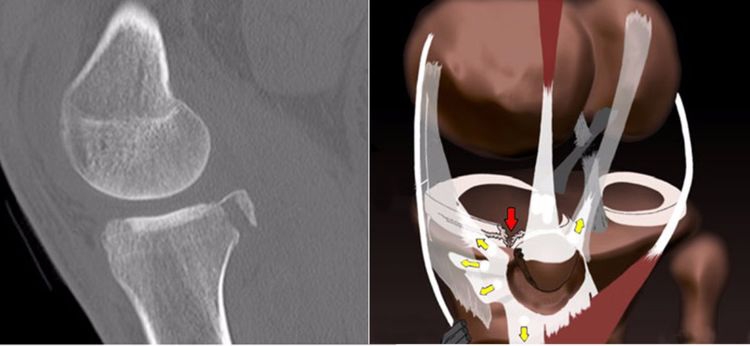

2.撕脱骨折:后交叉韧带胫骨附着点的撕脱骨折较常见。表现为胫骨平台后部有线形的T1加权低信号,T2加权,STIR高信号的骨折线,撕脱的碎片和后交叉韧带相连而韧带的连续性未见中断。

4.内侧胫骨平台撕脱骨折:胫骨平台前外侧撕脱骨折(Segond骨折)常常合并ACL损伤。而内侧胫骨平台骨折撕脱骨折则常常合并PCL损伤。

5.内后侧胫骨平台的撕脱骨折:国外也进行了相关的研究,主要是半膜肌的牵挂或股骨后髁与胫骨平台内侧缘撞击引起。

国外研究认为膝关节屈曲90°轴向载荷是导致胫骨平台后内侧骨折的一种创伤机制,因暴力的不同,既可合并PCL损伤,也可合并ACL损伤。